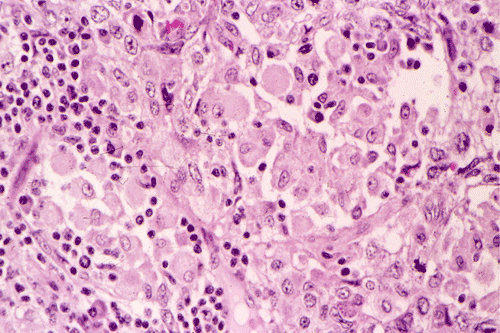

A survey at low-magnification shows a necrotic neoplasm (Panel F). The tumor cells arrange in different patterns. The tumor cells are densely packed in some areas but loosely packed in other areas.  At medium-magnification, several different patterns of architecture are disclosed. The most commonly encountered pattern in this case is a reticular-microcystic arrangement of cells (Panel G). In a significant amount of other areas, there are hypocellular to myxoid non-neoplastic stroma lined by a single layer of neoplastic cells (Panel H, I). The tumor cells have moderate to large nuclei with substantial pleomorphism. The chromatin is clumpy and hyperchromatic (Panel J). In some areas the tumor cells has an hepatoid appearance featured by a smaller nuclei with substantial amount of amphophilic cytoplasm (Panel K). Schiller-Duval bodies are occasionally noted (Panel L). A variable number of eosinophilic globules are also present and they are strongly positive for periodic acid-schiff (PAS) reaction (Panel M). Results of immunohistochemistry are as follows:

Yolk sac tumors exhibit a wide range of histologic patterns that differ considerably from each other. In most cases, a mixed histologic pattern is present and, not infrequently, one or two patterns may predominate. The most common pattern is the microcystic-reticular pattern. The other histologic patterns included endodermal sinus, solid, alveolar-glandular, polyvesicular vitelline, myxomatous, macrocystic, papillary, intestinal, hepatoid, and spindle cell. Although there is a rich variation in architecture, the variations in cytologic features are less impressive. The tumor cells are medium to large and have clear to pale, granular cytoplasm. Hobnail cells are not uncommon and often seen with the papillary pattern. The nuclei are large, vesicular, and contain prominent nucleoli. Yolk sac tumors are mitotically active. Necrosis and hemorrhage are common.

The microcystic-reticular pattern is characterized by a loose vacuolated network with small cystic spaces or microcysts that give rise to a meshwork of communicating space. The microcysts are lined by flat, pleomorphic, epithelium-like cells with large hyperchromatic or vesicular nuclei. The myxomatous pattern is similar to the microcystic pattern but is loosely packed and contains mucoid material.

Yolk sac tumor arising in the thymus often have extensive invasion into the adjacent tissue. In this cases, the tumor is still confined. The histology is quite typical for a yolk-sac (endodermal sinus) tumor. The reticular-microcystic pattern being illustrated here is the most common pattern being encountered.  Only a small number of Schiller-Duval bodies are present. The large cells with hepatoid look correspond to the hepatoid pattern in yolk sac tumor. The solidly arranged sheets of tumor raise the possibility of an embryonal carcinoma. However, the nuclear pleomorphism, although significant, is still short of that from embryonal carcinoma. The extracellular, PAS(+), eosinophilic hyaline globules are also typical for yolk sac tumor. These globules are often immunoreactive for a-fetal protein and a-1-antitrypsin. In our case, they are only positive for a-1-antitrypsin. The lack of CD30 immunoreactivity, again, does not support a diagnosis of embryonal carcinoma.